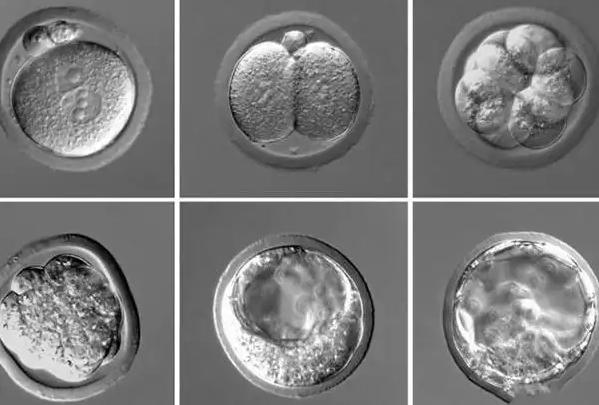

说到试管三代,你可能听说过试管婴儿技术分好几代,但其实这更多是个俗称。第三代试管婴儿,学名叫胚胎植入前遗传学诊断(PGD)或筛查(PGS)。它的核心在于,在胚胎移植前,医生会取几个细胞进行基因检测,看看有没有遗传病或者染色体问题。这样啊,就能提高成功率,避免一些先天性疾病。但注意哦,很多国家禁止非医学需要的性别选择,所以性别比例这个话题得谨慎对待。

好,现在咱们具体聊聊4个囊胚的情况。假设你做了试管三代,有4个囊胚送检,性别比例会怎样呢?首先,我得说,这没有固定答案。在PGD过程中,检测结果会告诉你每个胚胎的性别和健康状况。我曾经听说过一个真实案例:一对夫妻通过PGD检测了4个囊胚,结果发现是2个男性胚胎和2个女性胚胎——这正好符合理论比例。但另一方面,也有朋友分享,他们检测出3男1女或1男3女的情况,这完全看运气了。所以啊,别指望一定有“完美”比例,毕竟样本小,随机性大得很。